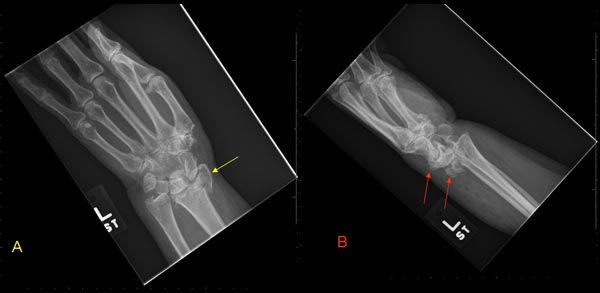

Frontal (A) and Lateral (B) radiographs of the left forearm and wrist demonstrate an intra-articular fracture of the radial styloid process (yellow arrow) with dorsal displacement of the fracture fragment and the carpal bones (red arrows). This fracture can be referred to as a 'combined Hutchinson (chauffeur) and dorsal Barton fracture' (a complex comminuted intra-articular fracture of the distal radius).